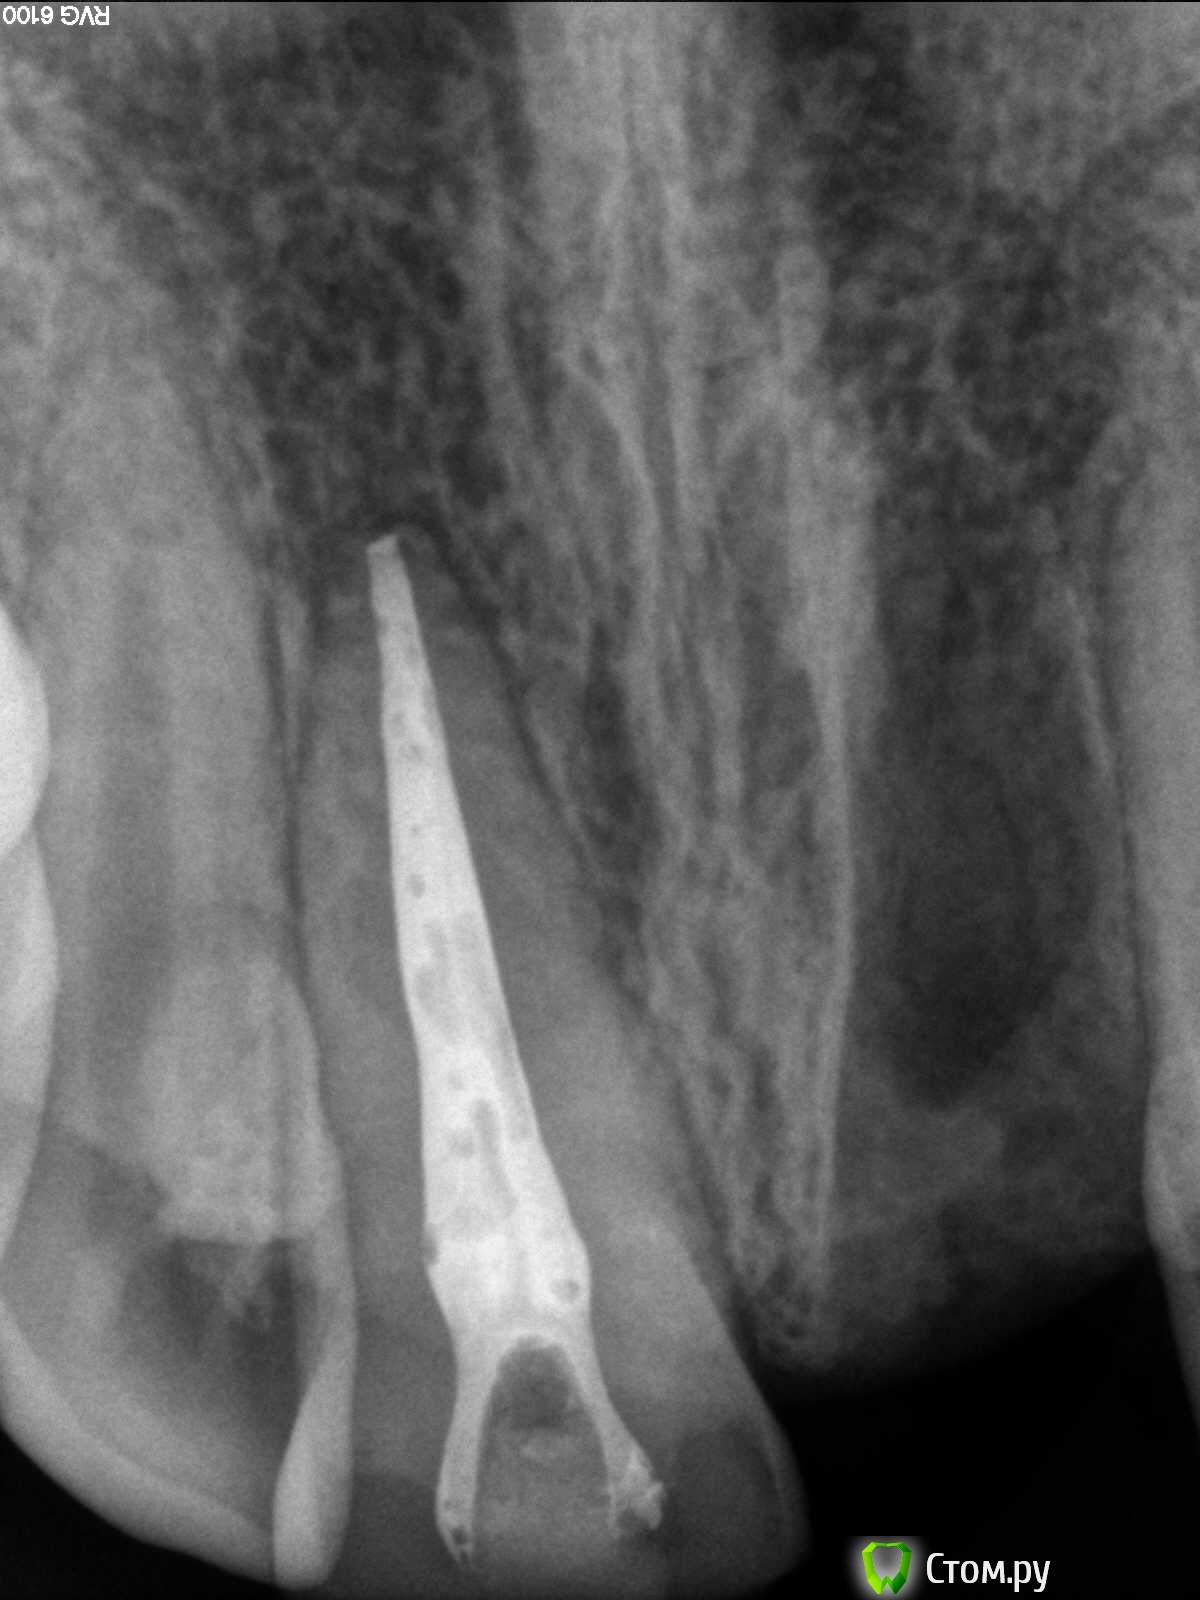

sorriso Опубликовано 31 мая, 2014 Поделиться Опубликовано 31 мая, 2014 В последнее время при обтурации получается вот такая картина. Раньше такого не наблюдала. Может быть партия силера такая? Кто как с этим справляется? Ссылка на комментарий

Гарриевич Опубликовано 31 мая, 2014 Поделиться Опубликовано 31 мая, 2014 Это не пору это "меньше сидера, больше силера" Ссылка на комментарий

АнтонТЛТ Опубликовано 1 июня, 2014 Поделиться Опубликовано 1 июня, 2014 Мне кажется нужно больше гутты Ссылка на комментарий

Kivilgar Опубликовано 1 июня, 2014 Поделиться Опубликовано 1 июня, 2014 Мне кажется нужно больше гутты+1 Ссылка на комментарий

Ico Опубликовано 2 июня, 2014 Поделиться Опубликовано 2 июня, 2014 В последнее время при обтурации получается вот такая картина. Раньше такого не наблюдала. Может быть партия силера такая? Кто как с этим справляется?Конусность 4ая? Ссылка на комментарий

sorriso Опубликовано 2 июня, 2014 Автор Поделиться Опубликовано 2 июня, 2014 Конусность 4ая?Нет,2ая Ссылка на комментарий

Ico Опубликовано 2 июня, 2014 Поделиться Опубликовано 2 июня, 2014 (изменено) Нет,2аяВы примерно помните как латералили и что за чем шло?Если да,опишите.Возможно просто недодавили))))))))У меня такое случалось,когда боялся овернуть Поры - не страшно,на результат мало влияют. Изменено 2 июня, 2014 пользователем Ico 1 Ссылка на комментарий

Ico Опубликовано 2 июня, 2014 Поделиться Опубликовано 2 июня, 2014 (изменено) и чего такая печалька случилась Там все наоборот)))) Это реколл через год!Бл.Спасибо исправил!!!! Изменено 2 июня, 2014 пользователем Ico 1 Ссылка на комментарий